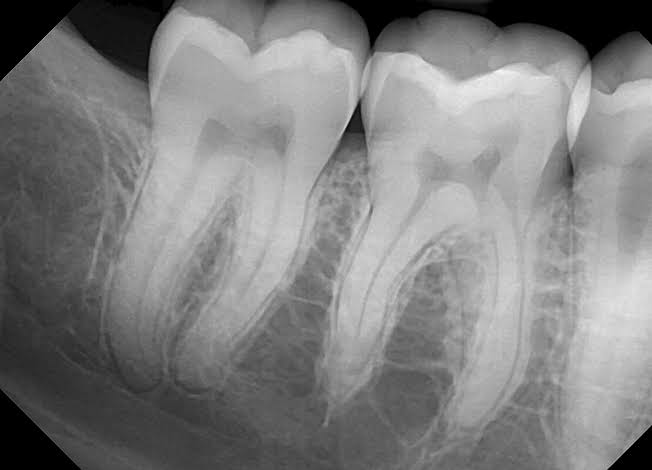

Discovered in 1895, radiographs are a crucial diagnostic tool in dentistry. They allow dentists to visualise images of the teeth, gums, and bones, identifying problems not visible to the unaided eye. Dental X-rays detect problems like cavities, decay beneath existing fillings, gum disease and infections in the early stages, allowing for prompt treatment, thus preventing progress of the disease and further complications. APPLICATIONS Assessment of Tooth and Bone Health: X-rays reveal the health of teeth and their supporting structures, including bone loss, impacted teeth, and other abnormalities. Treatment Planning:They provide crucial information for planning various dental procedures, including orthodontics, root canals, and implants. Evaluation of Oral Pathologies: X-rays can identify cysts, tumors, and other lesions, aiding in diagnosis and treatment strategies. Follow-ups: X-rays taken at regular intervals help to track the progress or healing of a lesion At Dr. Gallani’s Dental Care, we use the X-Mind Dental Xray and Carestream digital sensors along with lead aprons for the sharpest intraoral dental images with minimum exposure to ionizing radiation. If you need a dental xray, contact us on 08042754192 at Dr. Gallani’s Dental Care in Aundh or www.gallanidentalcare.com now!